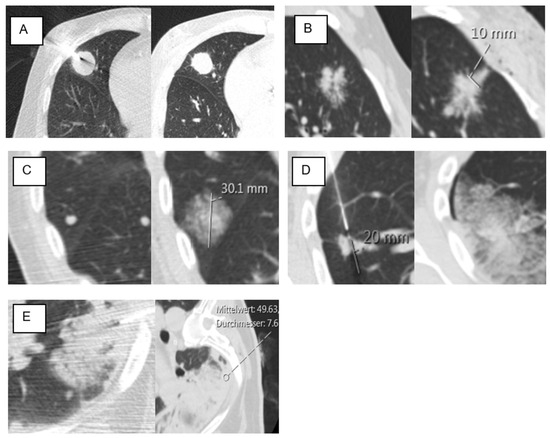

| Ground-glass in the access route | 46 | 40% | 26 | 31% | 20 | 67% | 0.001 * |

| GG in the access route | 1.643 | 0.514 | 10.233 | 1 | 0.001 * | 5.169 | 1.889 | 14.144 |